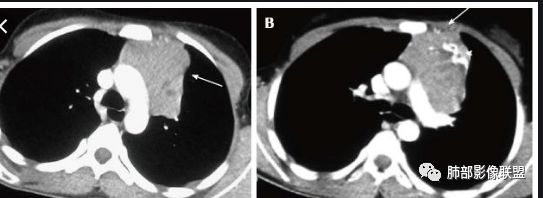

水晶石头:患者老年男性,发现皮肤粘膜黄染5天,右肺占位1天。

胸部CT:右肺中叶内侧段紧邻心脏实性结节,边缘光滑,边界清楚,宽基底与胸膜相连,内可见不规则钙化,钙化内见点状低密度影,增强中度强化,综合考虑良性病变。畸胎瘤可能大,鉴别胸膜孤立性纤维瘤及胸腺瘤。

王秀仙:右侧前纵隔肿块,边缘分叶,周围肺组织推移,宽基底与纵隔胸膜相连,可见胸膜尾征,密度不均,病灶中心可见斑块状钙化,右侧内乳动脉位于病灶前外侧并略增粗,实性成分明显强化,考虑纵隔畸胎瘤,鉴别胸腺瘤。

蓝天白云:定位纵隔,病灶呈实性成分,内见钙化,钙化位于病灶中心,实性成分均匀延迟强化,考虑良性病变,如果胸膜起源考虑sft,纵隔来源胸腺瘤,鉴别畸胎瘤。黄勇老师说过右侧心膈角区可以发生胸腺瘤